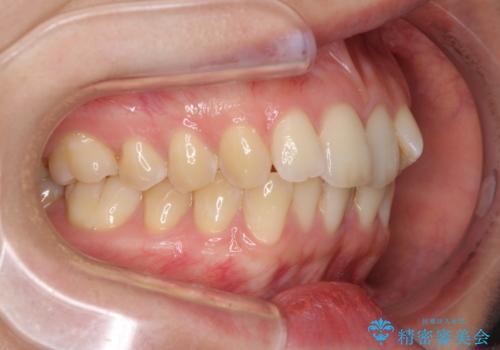

前歯のデコボコを解消 インビザラインによる矯正治療

- 上下前歯のデコボコと深い咬み合わせを気にして来院された患者様です。

インビザラインによる上下歯列の拡大と、IPR(歯と歯の間を削る)にるスペースの獲得により、前歯のデコボコを改善することとしました。

上の前歯をもう少し整えたかったのですが、患者様の治療を早く終了させたいという希望により、細かい叢生を残しての終了となりました。